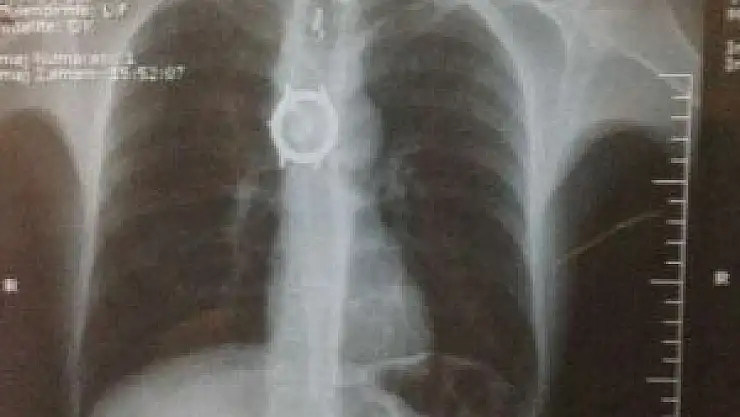

Van'ın Özalp ilçesinde yutma rahatsızlığı nedeniyle Yüzüncü Yıl Üniversitesi Dursun Odabaş Tıp Merkezi'nde ameliyata alınan bir kişinin yemek borusundan kol saati çıktı.

Erhan Özbilir’in rahatsızlığının artması üzerine yakınları tarafından YYÜ Dursun Odabaş Tıp Merkezi Göğüs Cerahi Bölümüne kaldırıldı. Burada Yrd. Doç Dr. Fuat Sayır ve Dr. Duygu Mergan İliklerden’in yapmış olduğu operasyonla Özbilir’in yemek borusundan daha önce yuttuğu kol saati, oyuncak ayının da bulunduğu 6 cisim tespit etti. Bunun üzerine Özbilir, hemen ameliyata alındı. Yapılan müdahale sonucu, Özbilir’in midesinden kol saati ve diğer cisimler çıkarıldı.

Bu tür vakaların ölümle sonuçlanabileceğinin altını çizen Dr. Duygu Mergan İliklerden, hasta yutma güçlüğü ve yemek yiyememe sorunuyla kliniklerine başvurduğunu söyledi. Yapılan tetkiklerde yemek borusunda yabancı cisimler olduğu tespit ettiklerini ifade eden Dr. İliklerden, “Hastanın filmlerini çektik ve içerisinde bazı cisimlerin olduğunu gördük. Hemen ameliyata alarak cisimleri çıkardık. Fakat saat parçası darlık nedeniyle yemek borusundan çıkmayınca hastayı açık cerrahiye aldık ve bu saati de çıkardık. Hastamız şu anda iyi sağlığına kavuştu" dedi.